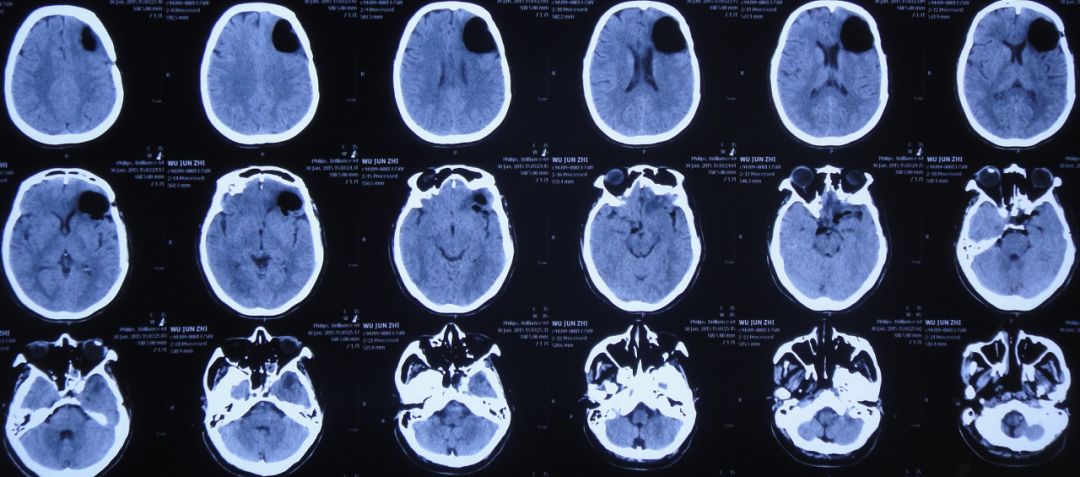

患者女,50岁,安徽省淮北市人。2014年12月14日,患者因高处坠落伤(2米左右)伤及头胸部及四肢,致昏迷,左耳、左鼻流血性液体,急诊前往安徽省淮南市潘集区某医院急查头CT显示左额叶脑挫伤、左侧颞骨凹陷性骨折、脑肿胀、颅内积气(图1);眼眶CT显示双侧眼眶内侧壁骨折(图2);胸部CT显示左侧肋骨骨折伴肺挫伤;右上肢X片显示右桡骨远端粉碎性骨折;左肩部X片显示左侧锁骨骨折。立即给予住院,保守治疗。

图1:2014年12月14日头CT:左额叶脑挫伤、左侧颞骨凹陷性骨折、脑肿胀、颅内积气

入院后第一天即2014年12月15日,患者神清,出现左眼肿胀,视力消失,左眼瞳孔增大,对光反射消失,左侧外耳道见澄清液体溢出,复查头CT:左额叶脑挫伤较前加重(图3)。

图3:2014年12月15日头CT:左额叶脑挫伤较前加重

入院后第二天即2014年12月16日为求进一步治疗,患者被转入淮南市某人民医院,查头CT:左额叶脑挫伤、脑组织弥漫性肿胀(图4);胸CT:双下肺感染(图5)。

图4:2014年12月17日头CT:左额叶脑挫伤、脑组织弥漫性肿胀、颅内积气消失

给予脱水、止血、营养神经、预防感染等保守治疗。之后约20天时间内,患者左耳溢液逐渐停止、左眼肿胀逐渐好转。但至外伤后19天即2015年1月2日,患者坐起后发现左鼻腔流液;复查头CT显示颅内大量积气(图6),给予保守、卧床、抗炎处理。

图6:2015年1月2日头CT:颅内大量积气

2015年1月12日,患者仍有脑脊液鼻漏;复查头CT:颅内积气有所减少(图7)。

图7:2015年1月12日头CT:颅内积气较前有所减少

2015年1月19日,患者仍有脑脊液鼻漏;复查头CT:颅内积气有所减少(图8)。

图8:2015年1月19日头CT:颅内积气有所减少

2015年1月26日转入中煤特殊凿井公司医院,继续半卧位保守治疗,治疗期间患者起床活动后仍有鼻腔流液现象,伴间断头痛。2015年1月30日复查头CT:左额颞软化灶形成,颅内积气明显减少(图9)。

图9:2015年1月30日头CT:左额颞软化灶形成,颅内积气明显减少

2015年5月18日患者因鼻腔流液增多,被转入徐州市某中心医院,头CT显示左额叶软化灶形成,颅内积气(图10)。

图10:2015年5月18日头CT:左额颞软化灶较前减小,颅内积气少量积气

2015年7月27日患者突发高热,体温高达39.0 ℃,伴呕吐,意识转差,腰椎穿刺颅内压力极高,并留取脑脊液进行细菌培养;复查头CT检查显示脑室系统显著扩张,颅内积气(图11)。当日急诊进行了右侧侧脑室钻孔引流术,术后入住ICU给予重症监护、抗炎、抑酸等治疗。

图11:2015年7月27日头CT:脑室系统显著扩张,颅内积气